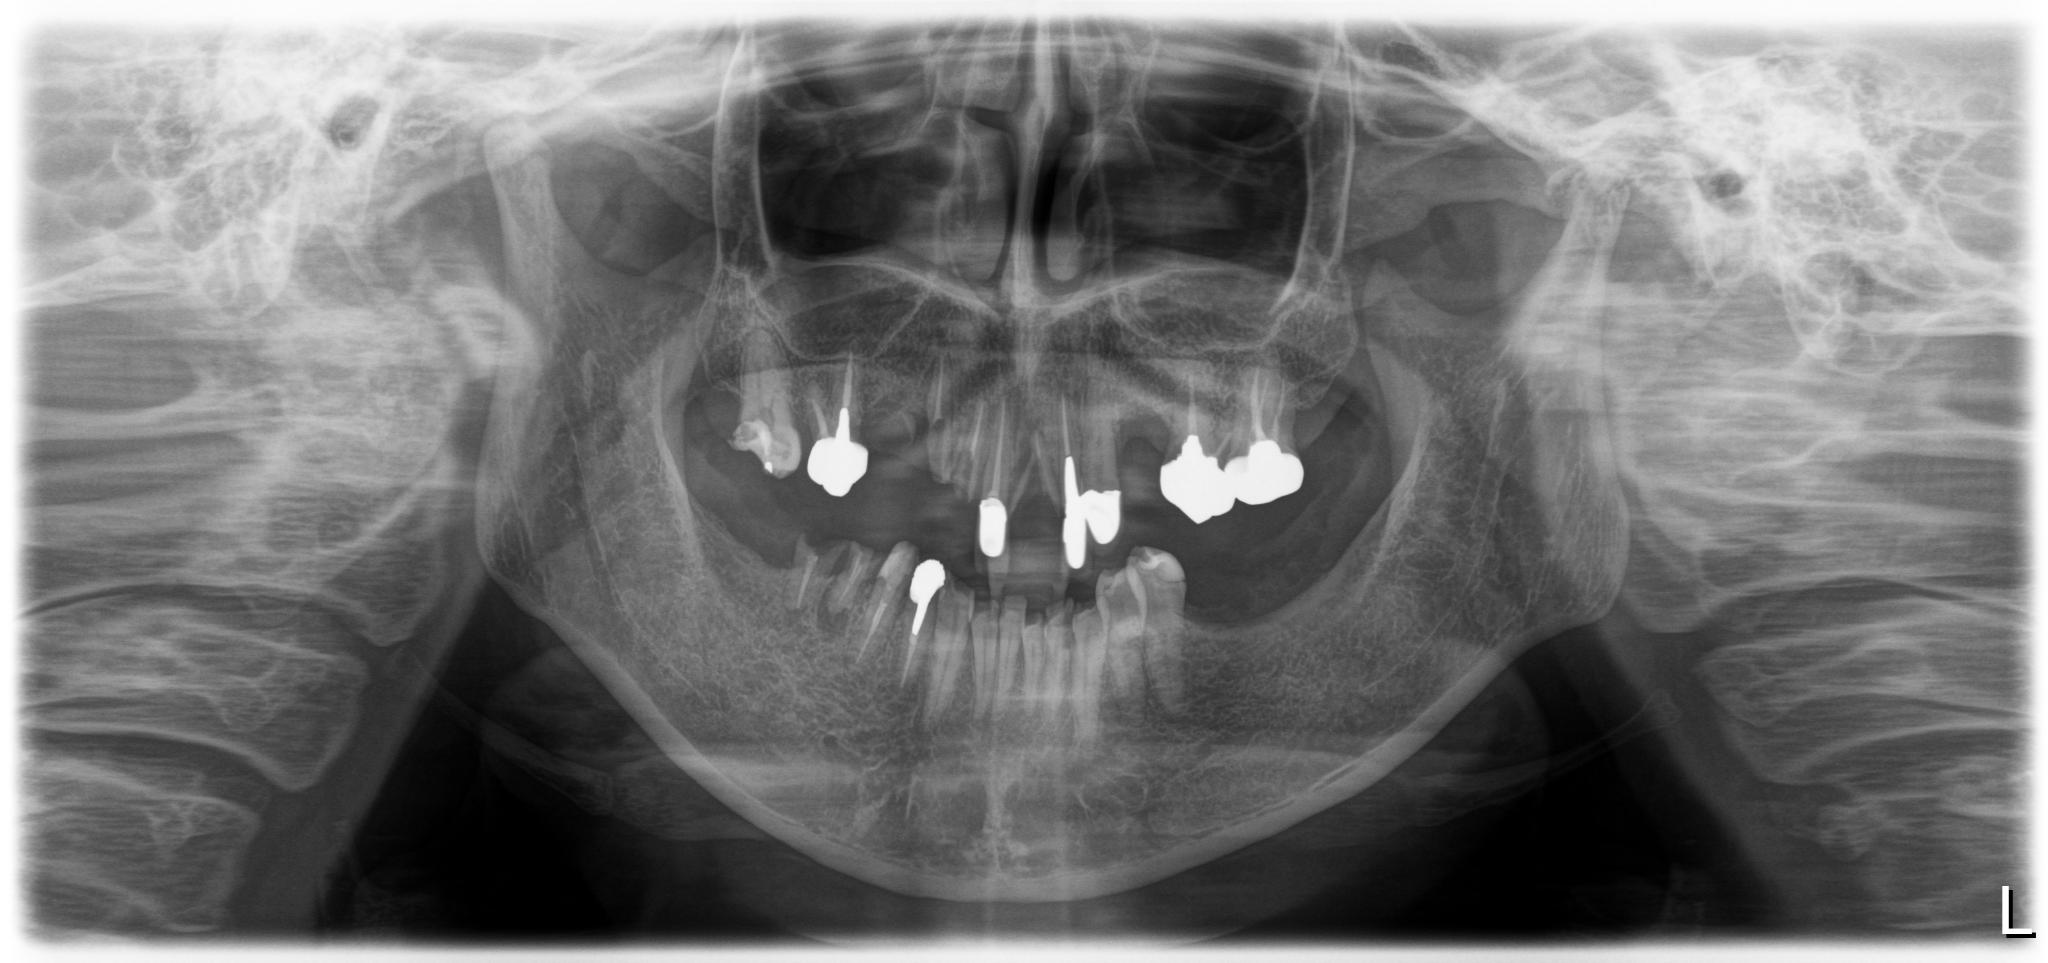

福岡県 49歳(男性)

「長年の口元の不安が負担」

術前

内容 :上下顎オールオン4ザイゴマ0

費用 :4,989,600円

※モニター価格

期間 :半年

リスク:出血・腫れ・痺れ・痛み

他院でインプラント治療を行っていましたが突然閉院となり、治療が中断されてしまいました。噛み合わせや歯並びに深刻な悩みを抱えることになり、口元の不安が負担になっていました。

相談の中でわずか1日で固定式の歯が入るスピード感に大きな魅力を感じました。

「ここなら長年の悩みが無くなるかもしれない」と感じ、手術を受ける決断をしました。

手術当日に歯が入り、その即時性に深く満足しています。これまでは人前で笑えないことが最大の悩みでしたが、これからは笑顔が増えていきそうです。